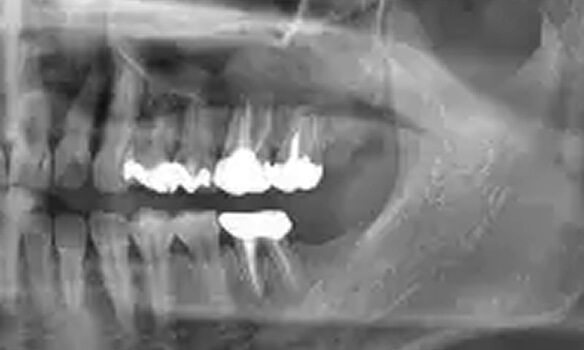

02.

精密検査

実際にお口の中の状態をチェックしていきます。レントゲン撮影にて歯や骨の検査を行い、虫歯や治療痕のチェック、歯周病検査などの各種検査を行い、総合的な診断を下します。

歯周組織再生療法

歯を残す最新治療

歯周病により破壊された、歯茎や骨を人工骨や成長因子などを用いて再生させる治療方法です。

将来的に抜歯となるリスクの高い歯などを歯周組織を再生させ、歯を長持ちさせることを目的とします。歯周病でダメになった歯をどうしても残したい方、歯ぐきや歯槽骨を元に戻して歯の寿命をしっかり伸ばしたい方に適応される治療方法です。 -